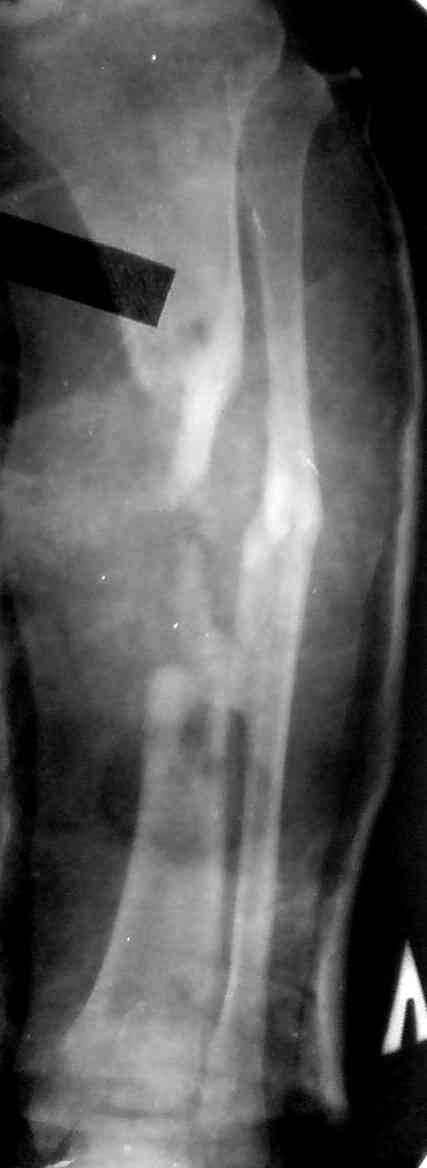

Пациент Г.,мужчина 56 лет, Хронический посттравматический остеомиелит

костей левой голени. Свищевая форма( Свищ в обдасти дистального

фрагмента по передней поверхности). Латентное течение. Дефект

большеберцовой кости в с/з 8 см.Ложный сустав малоберцевой кости

наьгранице с/з и в/з. Укорочение до 2,5 см.

Травма 16.11.2006г.- падение с высоты 6 м. Открытый перелом костей левой

голени. Был прооперирован стержневым аппаратом внешней фиксации.

Развился остеомиелит большеберцевой кости. Через 4 мес. после травмы

аппарат пришлось снять. Была проведена секвестрнекректомия(удален

фрагмент большеберцевой кости) и наложена циркулярная окончастая

гипсовая повязка

Планируется: Костная пластика губчастым аутотрансплантатом с целью

создания синастоза мало- и большеберцевой костей с стабилизацией

спице-стержневым аппаратом.